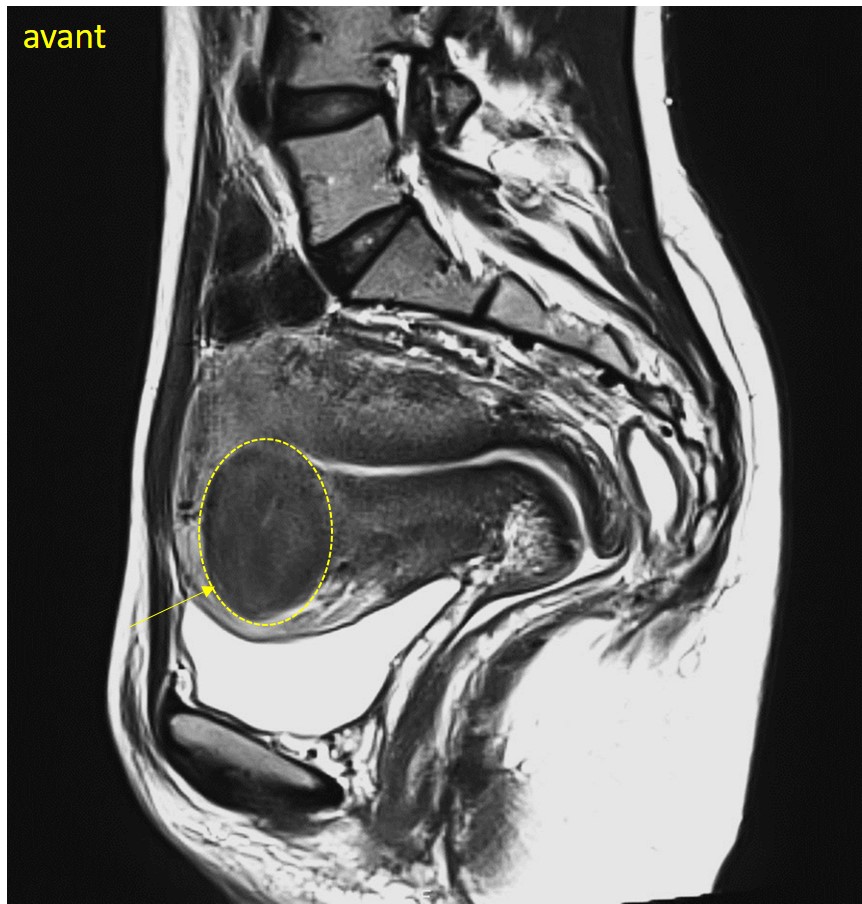

Les études montrent que la plupart des patientes voient leurs symptômes s’améliorer significativement dans les mois suivant l’intervention, avec une réduction durable de la taille des fibromes (diminution de leur volume > 70% en moyenne).

Une consultation de suivi de radiologie interventionnelle et une IRM sont programmées de manière systématique à 6 mois pour évaluer l’évolution de la taille des fibromes et s’assurer que l’embolisation a été efficace cliniquement.